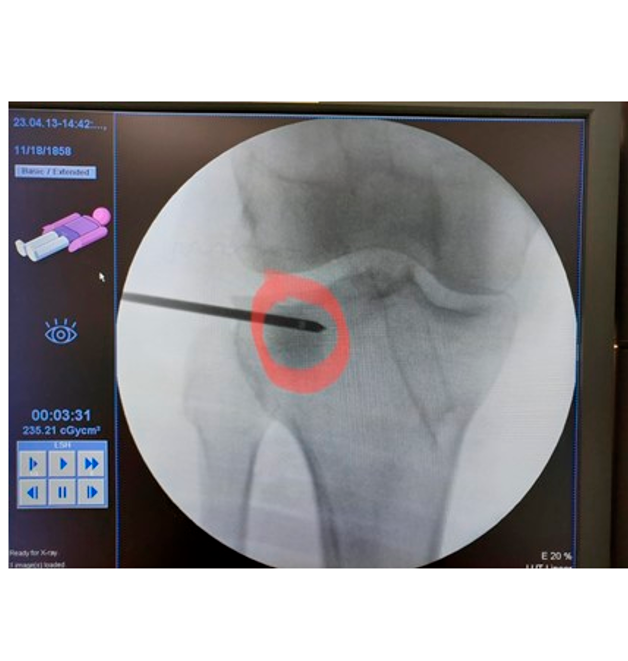

Nos casos em que o diagnóstico é feito tardiamente ou o tratamento conservador não é efetivo, temos agora um novo tratamento chamado subcondroplastia. Na subcondroplastia é injetado percutaneamente um concentrado de fosfato de cálcio no local da fratura que vai funcionar como um “cimento local “, dando suporte e retirando a dor do paciente em até 2 semanas.

Subcondroplatia: concentrado de fosfato de cálcio é injetado na região da fratura por fadiga guiado por um aparelho de RX (radioscopia)